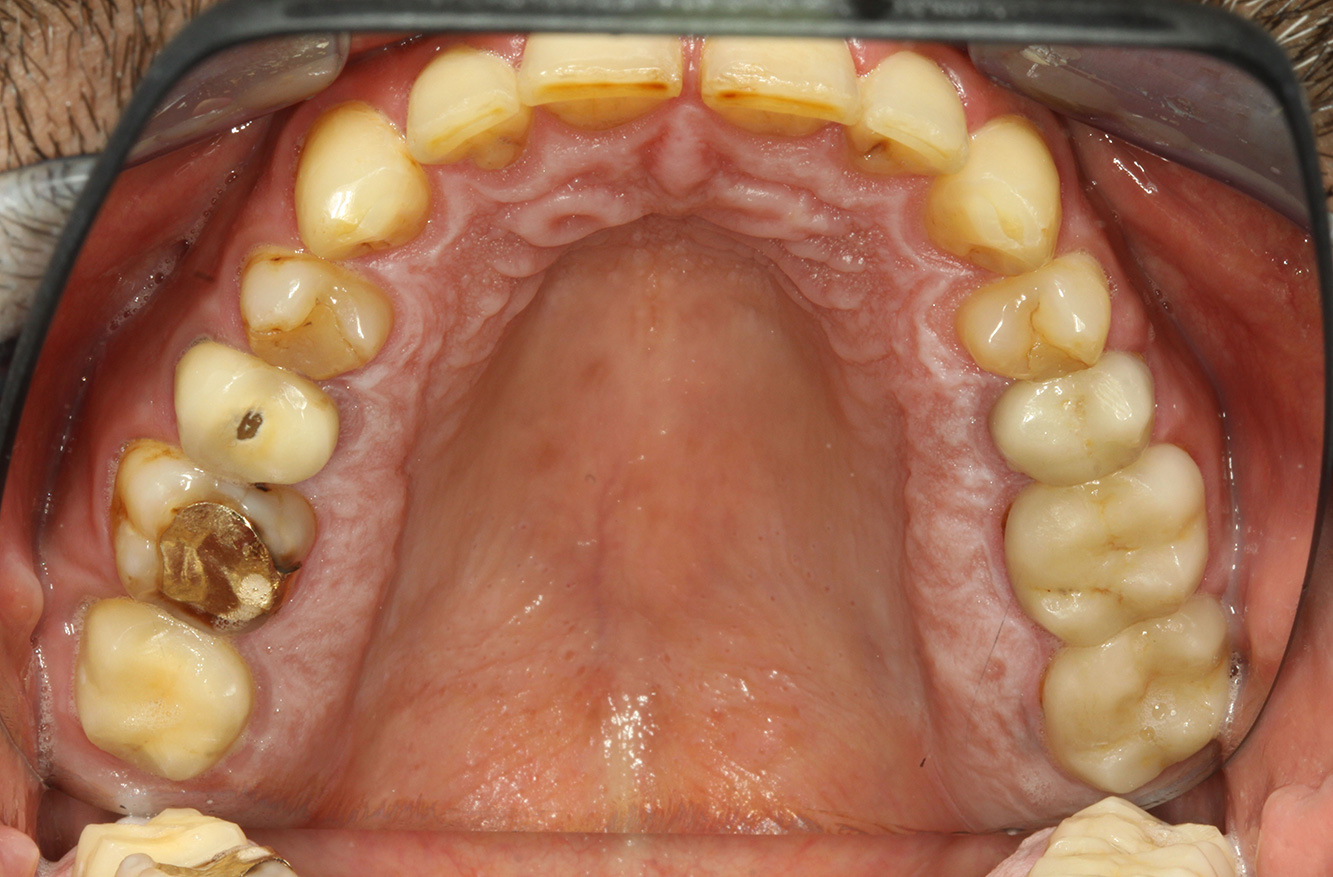

© Dr G. Schmalz y Dr D. Ziebolz MSc

El paciente tiene 39 años con valvuloplastia frente a una insuficiencia valvular y endocarditis. Toma regularmente ASS 100 (ácido acetil salicílico) como anticoagulante. En el ámbito del estilo de vida, la alimentación se identifica como promotora de caries, ya que suele consumir alimentos azucarados y seis o siete comidas al día. La salud oral del paciente muestra un riesgo medio de caries con lesiones activas. El riesgo de periodontitis es bajo, presenta gingivitis. Se hacen las siguientes recomendaciones para el tratamiento profiláctico.